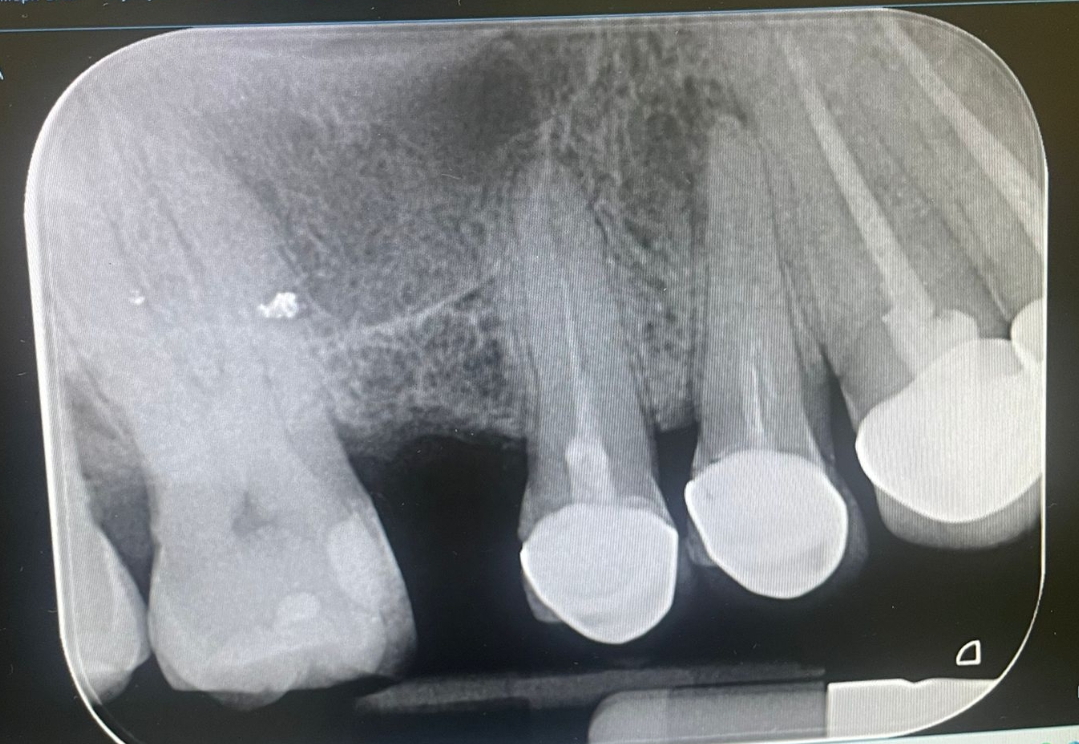

Здравейте!Ляв шести зъб ,лекуван е октомври месец.От няколко дни имам парене около зъба ,неприятно усещане не точно болка.Има ли инфекция ,какви са тези три точки на корена на зъба?